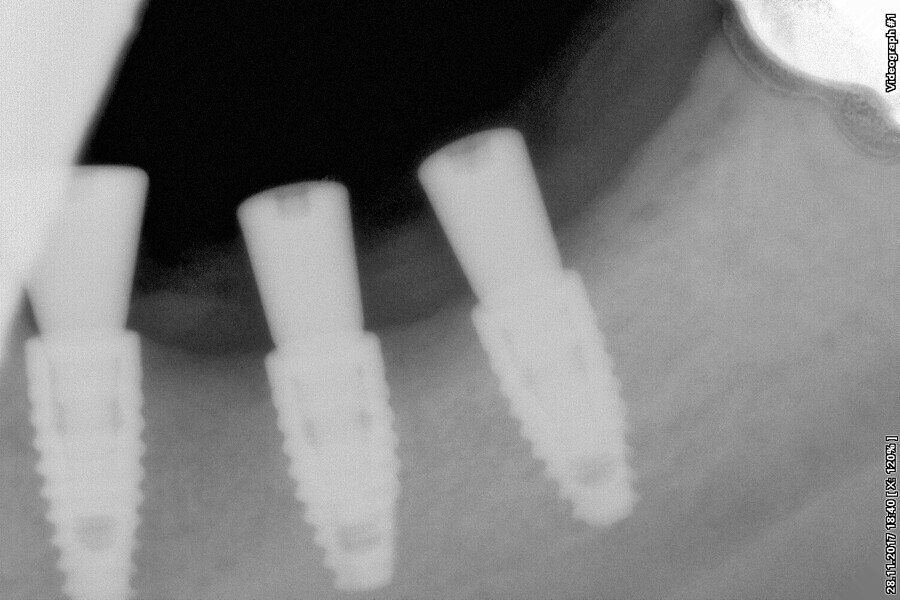

Fig. 11: Post-op dental panoramic tomogram.